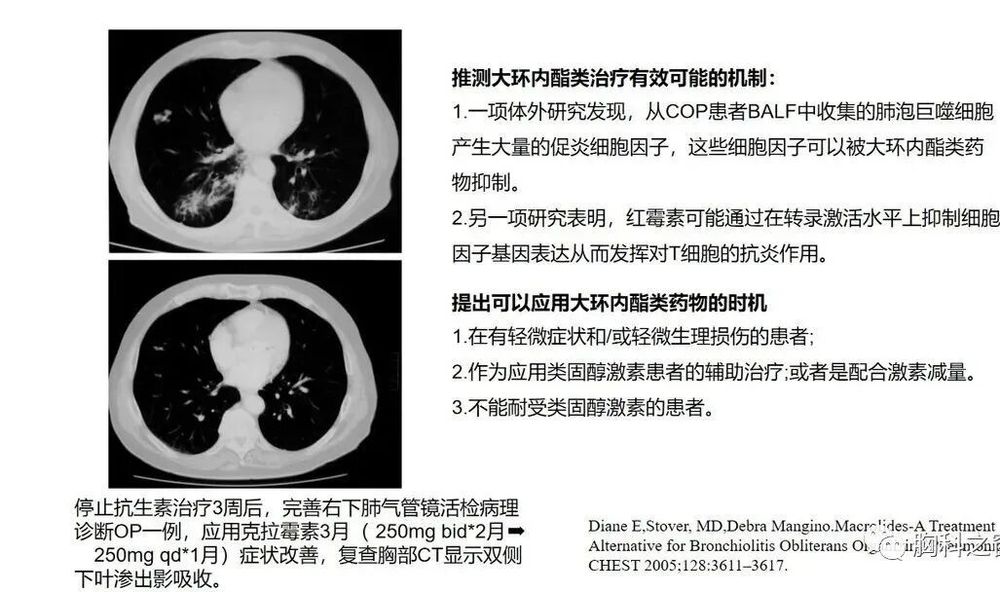

少数COP患者可自行缓解,对于一些无症状或症状轻微的COP患者,单纯使用大环内酯类药物如克拉霉素、红霉素治疗后症状即可改善。激素是目前治疗COP的主要措施,临床症状一般在48h内得到改善,影像学病变常常在几天内明显吸收。激素治疗原则是早期、足量、足疗程,以减少并发症,降低复发率和病死率。激素起始用量,泼尼松60mg/d或0.75~1mg/(kg·d),时间1~3个月,逐渐减量至20~40mg,时间为3个月,维持剂量为泼尼松5~10mg/d,后期可改为泼尼松5mg,隔日1次。

大环内酯类抗生素

病例报告和小规模回顾性病例研究提示,在COP患者中,具有抗炎特性的大环内酯类抗生素(如红霉素或克拉霉素)可作为口服糖皮质激素的辅助方案或替代方案。

大环内酯类抗生素通常用药3~6个月或更长时间,并在停止治疗期间密切监测,以防复发。大环内酯类药物单独使用效果不佳,且适当的剂量和持续时间有待确定。